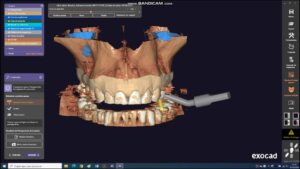

A importância do planejamento digital cirúrgico A importância do planejamento digital cirúrgico é visar previsibilidade do tratamento, evitando intercorrências e